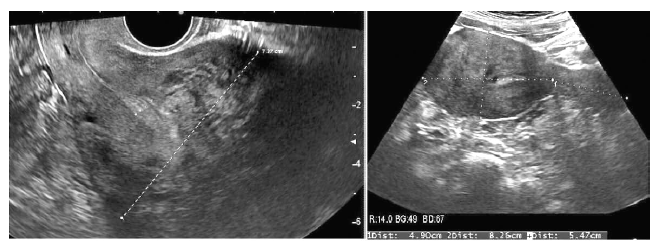

This patient first visited this center in February 2016. At that time, she had been married for 3 years and was 33 years of age. Before the visit, she had undergone treatment with three cycles of intrauterine insemination and one cycle of IVF at another center. She had never been pregnant and had no specific medical history. Her interval of menstruation was irregular from 30 days to 90 days with menorrhagia and dysmenorrhea. On the ultrasonogram taken on the first visit, her uterus was enlarged to 7.7 cm × 17.5 cm with adenomyosis and multiple myomas (Figure 3). Her hormonal profile was as follows: AMH level, 5.59 ng/mL, FSH level, 4.64 mIU/mL, prolactin level, 7.50 ng/mL, and estradiol level 45.6 pg/mL. Semen analysis indicated that semen motility was decreased to 33%.

Figure 3.— Case 3: sonograms of the uterus before and after D2 agonist and gonadotropin releasing hormone agonist treatment. The size of the uterus is significantly reduced after the treatment.

She was prescribed bromocriptine from the first day of her visit for 4.5 months; 1.25 mg once daily for a week, twice daily for another week, and then the dosage was adjusted to 2.5 mg twice daily for 120 days. She was simultaneously treated with three cycles of the GnRH analog. After treatment, her dysmenorrhea was relived from an NRS of 10 to an NRS of 1, and the size of her uterus was reduced to 4.9×13.7 cm (Figure 3). Laparoscopic myomectomy and tuboplasty, and hysteroscopic polypectomy were performed before initiating IVF. Five months postoperatively, IVF was conducted and 12 eggs were retrieved, of which four were fertilized. Among them, two embryos were transferred, resulting in pregnancy. The endometrium thickness was 1.5 cm before ET, and the grade of the embryos was 8CG1. Unfortunately, a spontaneous abortion occurred at the gestational age of 10+3 weeks.